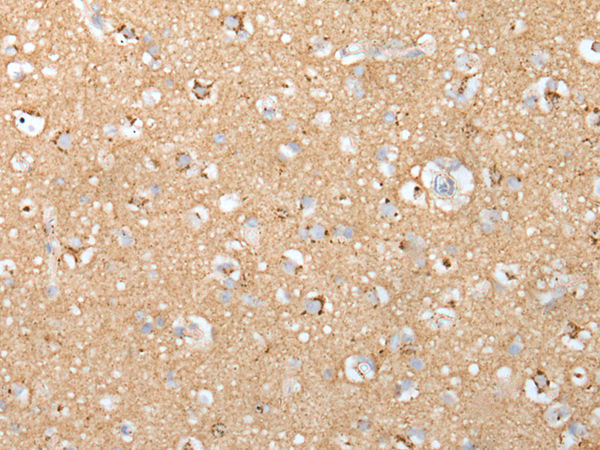

分类: 科研抗体货号: P02445别名: CLI; AAG4; APOJ; CLU1; CLU2; KUB1; SGP2; APO-J; SGP-2; SP-40; TRPM2; TRPM-2; NA1/NA2应用: IHC反应种属: Human, Rat